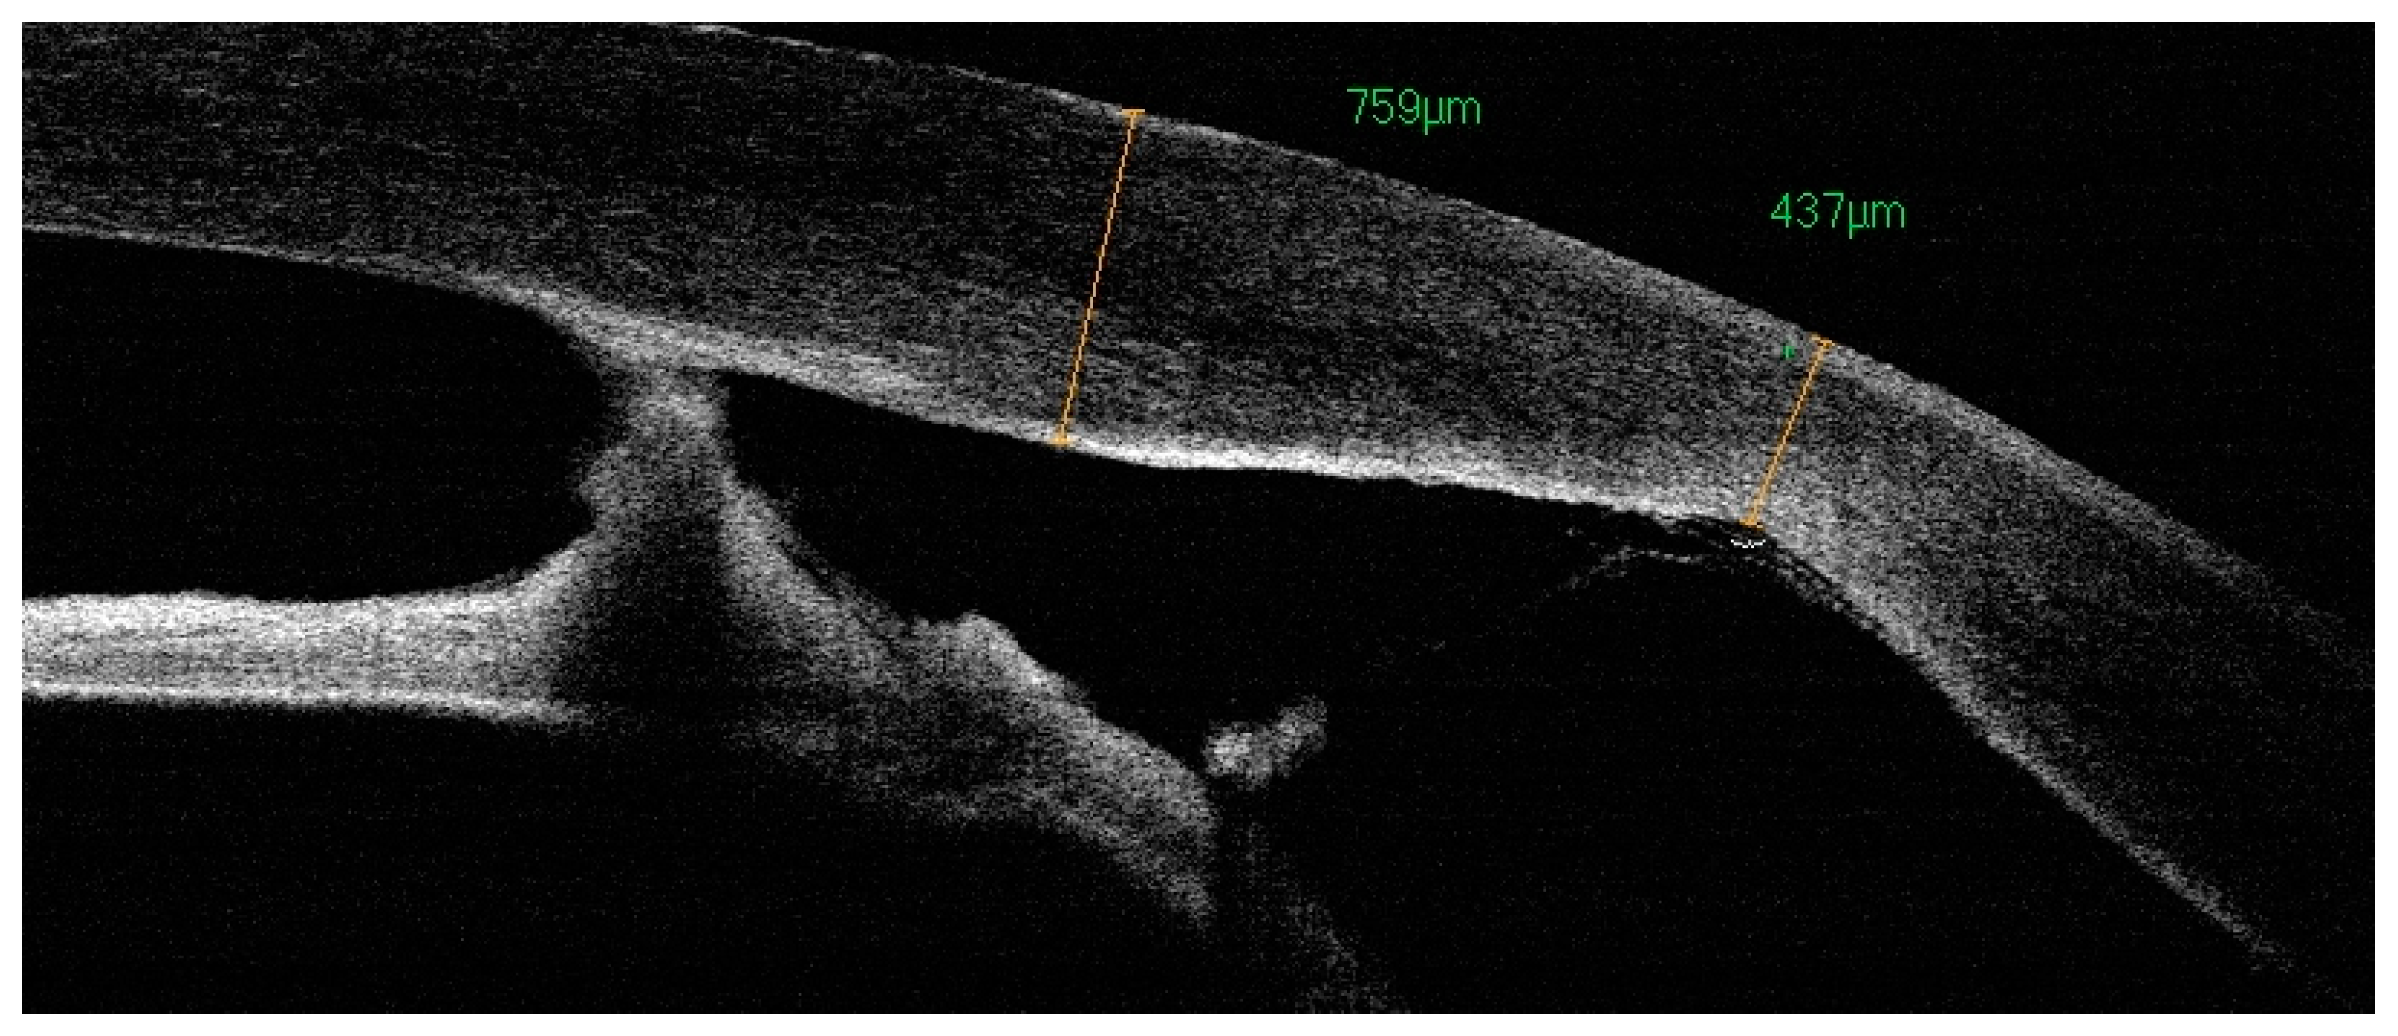

Figure 3.

OCT: irregular corneal thickness and corresponding iris-endothelial adhesions.

Figure 8.

The same patient, LE. OCT: variable corneal thickness, increased within the adhesions (600–700 um), anterior adhesions, corresponding clouding, and defects in the posterior layers of central and paracentral cornea.